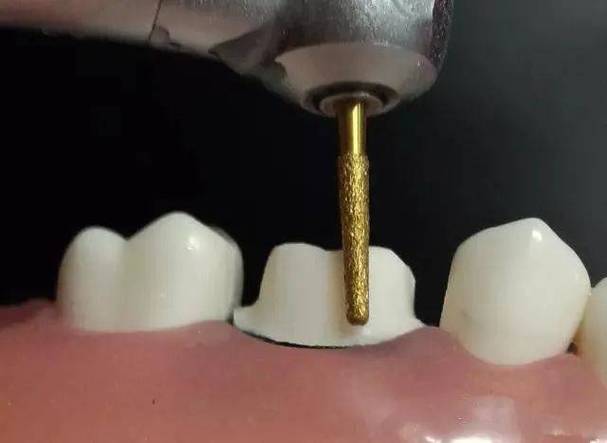

- 预备工具:直角肩台预备车针(如896号、TR-13号)或火焰形车针。

- 沿牙颈部牙龈缘下方1.0mm处,用车针垂直于牙体长轴磨出1.0-1.5mm深的沟槽,内线角圆钝,避免尖锐转折;

- 修整沟槽底部,确保宽度均匀,无肩台中断或台阶。